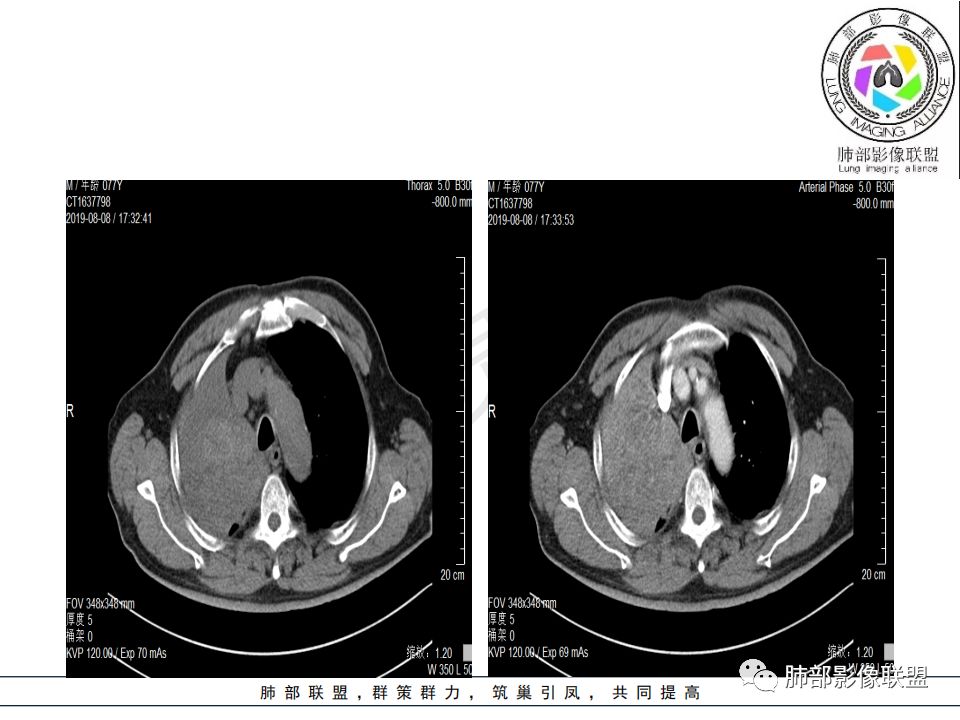

右肺主支气管有软组织肿块,向腔内外生长,右肺上叶肺不张,边缘光滑,增强扫描不均匀强化。考虑恶性肿瘤,鳞癌可能。

晨读,右肺主支气管有阻塞,腔内.腔外都见软组织影,右肺上叶不张,肿块内部密度不均匀,是不是有坏死影,老年男性,考虑恶性~鳞癌

影像:影像右侧大支气管阻塞,临床没有症状或很轻微,要想到胃腺癌转移;胸壁代偿好,透亮度稍低不明显,慢性过程;34.8-52.5HU,主病灶支气管前壁另有1结节,都做成增强两期了,动脉期较平扫有强化;

晨读:患者老年男性,以咳嗽一月就诊,少量白痰,胸CT:纵隔右移,右肺体积缩小,气管下段管壁可见结节样改变,气管软骨变形,气管下段及右主支气管可见新生物向管壁浸润,并向管腔外生长,右上肺肺不张,但不张边缘可见病灶呈膨胀性生长,可见分叶,增强后强化明显。考虑:肺部恶性病变(鳞癌?)

右肺上叶肿块,边缘光滑,略膨隆,近段支气管堵塞,平扫密度均匀,增强后不均匀强化,其内可见不规则血管和坏死,纵隔淋巴结肿大,老年男性,无感染性病史,综合考虑恶性肿瘤(鳞癌,腺癌),鉴别:OP(一般下叶多见)

从强化情况和冠状位看主要还是从外向内的一个肿块,有不张,但不张范围不大,近端支气管堵塞,考虑腺癌或类癌(原发或转移都可能),鉴别鳞癌。

1.右肺上叶较大块影,密度不均,轻度强化并见低密度区,所属支气管截断并腔内突入,是符合肺鳞癌的影像学特征和生物学行为的。